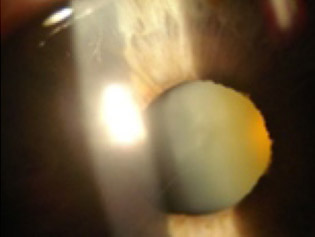

Selecciona una imagen y la respuesta correcta para cada uno de los reactivos, de acuerdo con el tipo de iluminación y la alteración o estructura que se muestre.